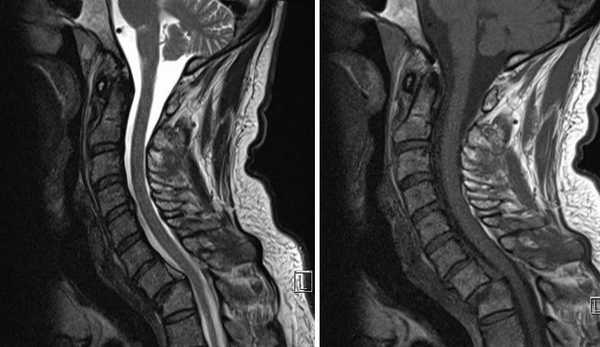

МРТ шейного отдела позвоночника в сагиттальной плоскости. Имеется смещение тела С7 позвонка кпереди относительно тела Th1 позвонка. Тело С7 позвонка без признаков отека костного мозга. Отмечается компрессионный перелом тела Th1 позвонка, преимущественно за счет неровности передне-верхней замыкающей пластинки. Спинной мозг однородной структуры.

Атланто-аксиальная дислокация

Это нарушение соотношения между первым и вторым шейным позвонками. Чаще всего − это смещение атланта вперед по отношению к аксису.

Не является самостоятельным заболеванием, а появляется как следствие травм и некоторых патологий (ревматоидное поражение, несовершенный остеогенез, болезнь Марфана, травмы).

На КТ и рентгенографии за счет наложения других костных структур (сосцевидный отросток, нижняя челюсть) диагностика может быть неверной, поэтому вывихи часто диагностируют спустя несколько лет после травмы. За это время позвонки жестко фиксируются в неправильном положении, что делает невозможным их безоперационное вправление.

При данной патологии принципиально важно оценить состояние связочного аппарата, что позволяет сделать только магнитно-резонансная томография.